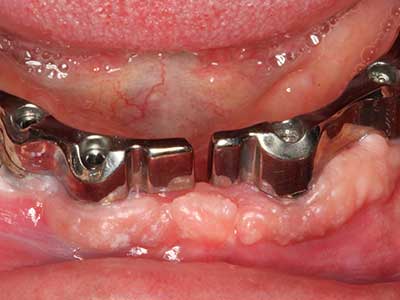

Il tessuto osseo non è semplicemente una struttura minerale, ma contiene anche una percentuale significativa di fibre di collagene. Ciò significa che non possiede solo una buona forza di compressione, ma anche un certo livello di flessibilità che è possibile sfruttare durante l'esecuzione degli accrescimenti di osso. Nella procedura di espansione classica con incisione ossea, la cresta alveolare atrofizzata viene incisa longitudinalmente ed espansa con cautela dopo aver raggiunto una profondità di osteotomia adeguata (figg. 13-16), idealmente senza una sostanziale rimozione del periostio (Brugnami, Caiazzo et al. 2014, Stricker, Fleiner et al. 2014). I sistemi a piastra e vite con distanza di espansione incrementale si sono dimostrati efficaci nella separazione delle due lamelle ossee restando al di sotto della soglia di frattura. In generale, sono richieste larghezze dell'osso residuo di almeno 3-4 mm (Chiapasco, Zaniboni et al. 2006) per garantire un'adeguata flessibilità e una copertura sufficiente dell'osso per gli impianti futuri. Se necessario, un'osteotomia di rilascio verticale su uno o più lati può migliorare la flessibilità. Una combinazione con ulteriori tecniche di accrescimento, in particolare dal lato buccale, è stata descritta come un'alternativa alla tecnica classica.

La procedura di incisione è particolarmente atraumatica e non comporta una perdita significativa di dimensione durante l'utilizzo delle seghe piezoelettriche, così come non si notano differenze rilevanti tra impianti in mandibole incise e impianti in una cresta alveolare senza deficit osseo (Chiapasco, Zaniboni et al. 2006, Danza, Guidi et al. 2009). Una sufficiente irrigazione continua è essenziale, tuttavia, in particolare con incisione profonda e localmente ristretta, per prevenire la sollecitazione termica nelle regioni apicali dell'osteotomia.